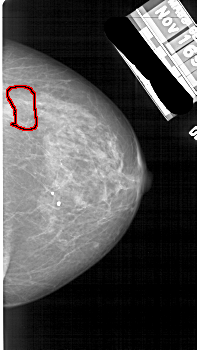

A_1889_1.LEFT_CC

RIGHT_CC LINES 4891 PIXELS_PER_LINE 2746 BITS_PER_PIXEL 12 RESOLUTION 43.5 OVERLAY

FILE: A_1889_1.RIGHT_CC.OVERLAY

TOTAL_ABNORMALITIES 1

ABNORMALITY 1

LESION_TYPE MASS SHAPE IRREGULAR MARGINS ILL_DEFINED

ASSESSMENT 4

SUBTLETY 4

PATHOLOGY BENIGN

TOTAL_OUTLINES 1

BOUNDARY